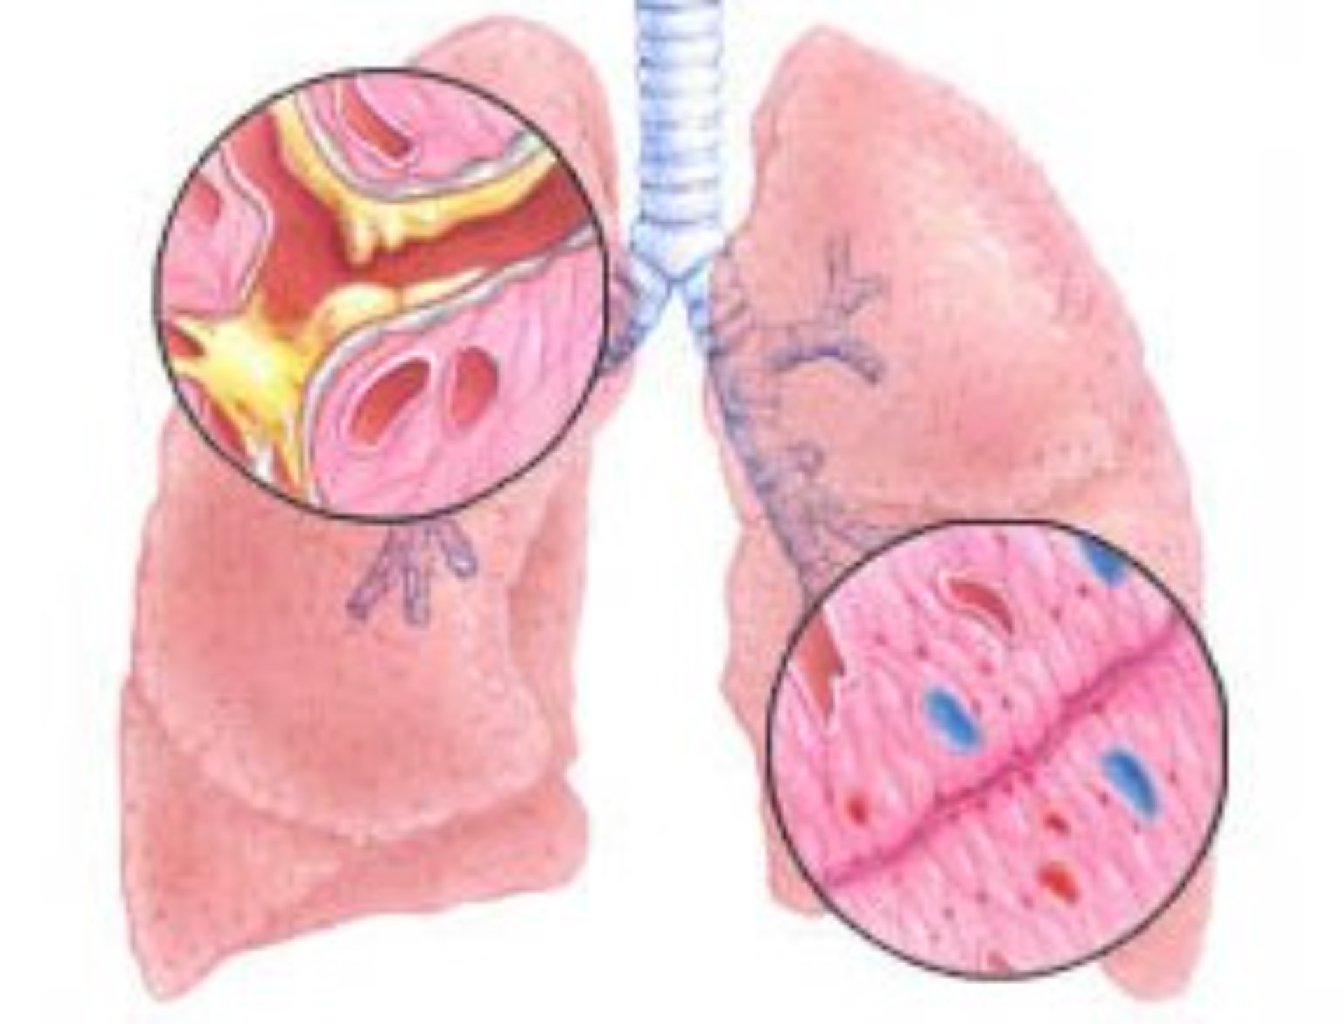

Alveolların zədələnməsi: Ağciyərlərdəki alveollar normal olaraq hava ilə doldurulur və boşalır, oksi ...

Bronxitin Səbəbləri və Növləri Akut Bronxit: Üstün yol infeksiyalarının, xüsusilə virusların n ...